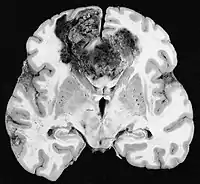

Examen macroscópico

A pesar de la corta duración de los síntomas, los glioblastomas suelen ser grandes en el momento de la presentación y pueden ocupar más de un lóbulo. La lesión es en general unilateral, aunque las del tronco cerebral y el cuerpo calloso pueden tener simetría bilateral. El tumor ocupa la misma posición en los dos hemisferios y muestra un aspecto de "mariposa". La extensión supratentorial bilateral se debe a un rápido crecimiento a lo largo de las estructuras mielinizadas, en particular a través del cuerpo calloso y a lo largo del fórnix hacia los lóbulos temporales. Los límites de la masa neoplásica, que no está encapsulada, son difusos por todas partes. La coloración es grisácea, pero pueden encontrarse abundantes variaciones de color, causadas por necrosis o hemorragias más o menos recientes, por lo que sobre el fondo gris aparecen zonas amarillentas, por degeneración grasa o necrosis y zonas de color rojizo o negruzco debidas a hemorragia.

La zona periférica del tejido tumoral hipercelular aparece como un borde suave y gris. El tejido necrótico puede bordear estructuras cerebrales adyacentes sin una zona tumoral intermedia detectable macroscópicamente. La necrosis central puede ocupar más del 80 % de la masa total del tumor.

Los glioblastomas están generalmente salpicados de manchas rojas y marrones debidas al sangrado. A veces son lo suficientemente grandes como para causar síntomas similares a un accidente cerebrovascular, que puede ser el primer signo clínico del tumor. Los quistes macroscópicos, cuando están presentes, contienen un fluido turbio proveniente del tejido tumoral necrótico licuado, en claro contraste con los quistes de retención bien definidos de los astrocitomas difusos de grado II.

La mayoría de los glioblastomas de los hemisferios cerebrales son claramente intraparenquimatosos, con epicentro en la materia blanca. A veces la neoplasia se presenta como ampliamente superficial y en contacto con leptomeninge y duramadre, y se puede confundir con un carcinoma metastásico o con una lesión extra-axial, como el meningioma.[11][60]